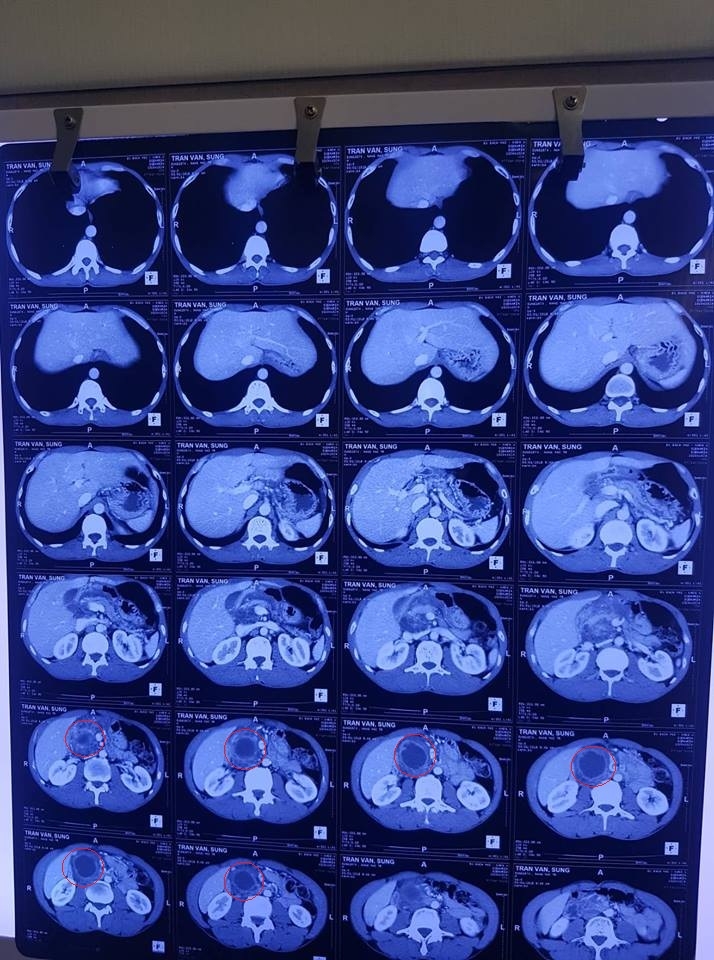

Chụp CT: Tổn thương U vùng đầu tụy dạng đa nang, nang lớn nhất KT 4,5×4,3cm.

Kết quả trước uống Kilcel 500mg